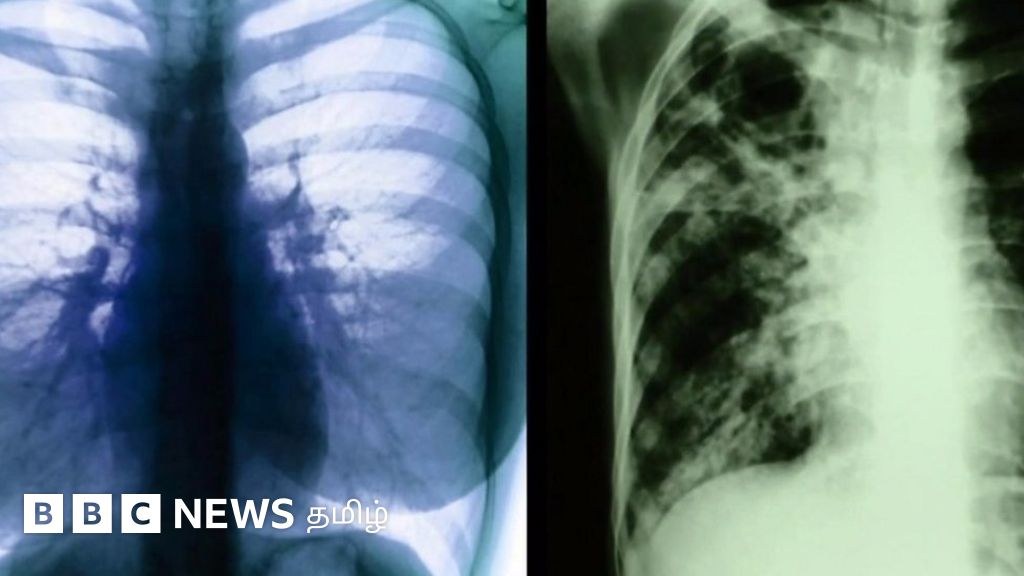

காசநோயை கண்டறிய புதிய வழி; பிரிட்டிஷ் விஞ்ஞானிகள் சாதனை

காசநோயை கண்டுபிடித்து சிகிச்சையளிக்கும் முறையில் பிரிட்டன் விஞ்ஞானிகள் மிகப்பெரிய கண்டுபிடிப்பு ஒன்றை நிகழ்த்தியிருக்கிறார்கள்.

உலகிலேயே முதல்முறையாக மரபணு மூலக்கூற்று கட்டமைப்பை பயன்படுத்தி காசநோயை துல்லியமாகவும் விரைந்தும் கண்டுபிடிக்க இவர்கள் வழி செய்திருக்கிறார்கள்.